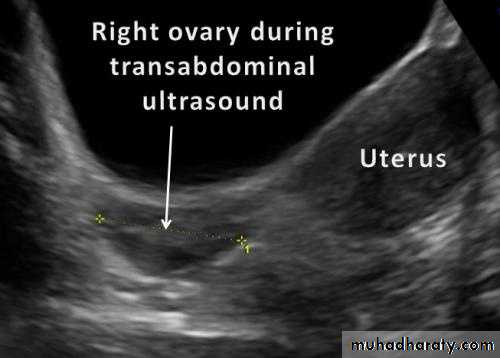

Ultrasound of Normal ovary

Normal Ovary